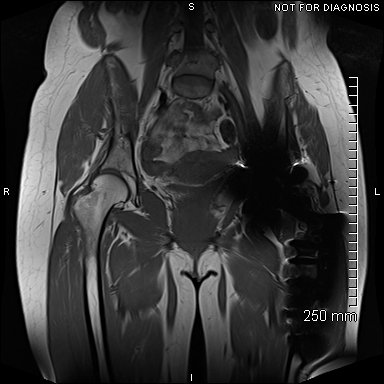

Coronal MRI showing left sided gluteal muscle wasting but no signs of loosening. There were no other abnormalities.